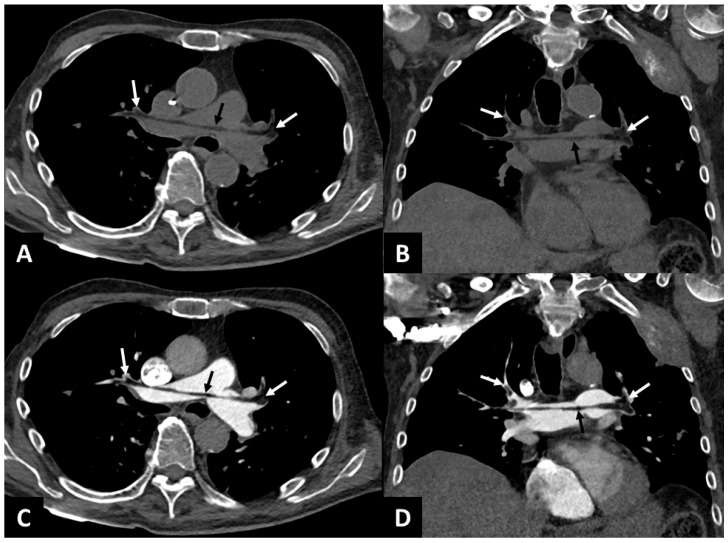

非对比胸部CT示肺近端脂肪栓塞。

我们报告这个临床病例,在未增强的胸部计算机断层扫描(CT)上发现近端肺脂肪栓塞,导致左全髋关节置换术治疗股骨颈骨折时心脏骤停恢复。这一观察结果强调了在骨科术后背景下整合胸部CT非对比期的诊断价值,因为它确保准确识别肺动脉血栓的脂肪性质,从而有助于提高诊断准确性和鉴别诊断。

We report in this clinical case a proximal pulmonary fat embolism detected on unenhanced chest computed tomography (CT) responsible for a recovered cardiac arrest during a left total hip arthroplasty for a femoral neck fracture. This observation underscores the diagnostic value of integrating a non-contrast phase in chest CT in the postoperative context of orthopedic surgery, as it ensures accurate identification of the fatty nature of pulmonary arterial thrombi and thereby contributes to improved diagnostic accuracy and differential diagnosis.